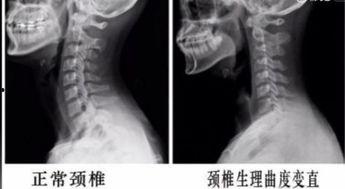

你是不是也和我一样,长时间对着电脑,颈椎开始抗议了?...